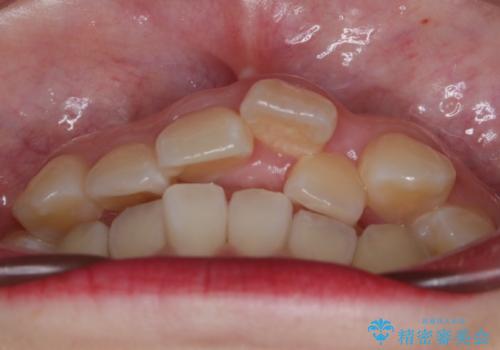

- 前歯のガタつきと口元の改善を主訴に来院されました。

なるべく目立たない装置が良いというご要望と、口元を引っ込めたいというご要望を両方達成するために今回はハーフリンガル装置を選択し治療計画の立案を行いました。

結果的に表の装置よりは期間が掛かりましたが、口元もしっかり下がり韓国美人な横顔になったと患者様にも喜んでいただけました。